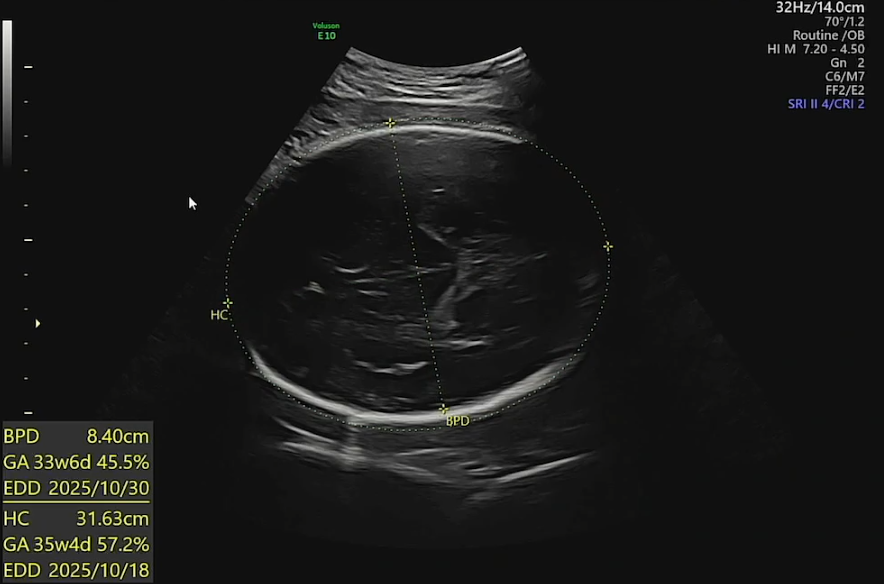

측정지표 해석

- BPD (Biparietal Diameter, 머리 양쪽 지름): 8.40 cm → 33주 6일 크기, 45.5 percentile

- HC (Head Circumference, 머리둘레): 31.63 cm → 35주 4일 크기, 57.2 percentile

3주 씩이나 앞서 크던 머리는 이제 좀 안정을 찾아간다. 31주까지는 왕-왕-하고 커지더니, 출산 위치로 자세를 돌리고서는 머리가 골반에 꼭 껴 있는지 머리둘레의 성장이 더뎌졌고(다행스런 일), 목도리처럼 두르고 있던 탯줄도 풀렸다.